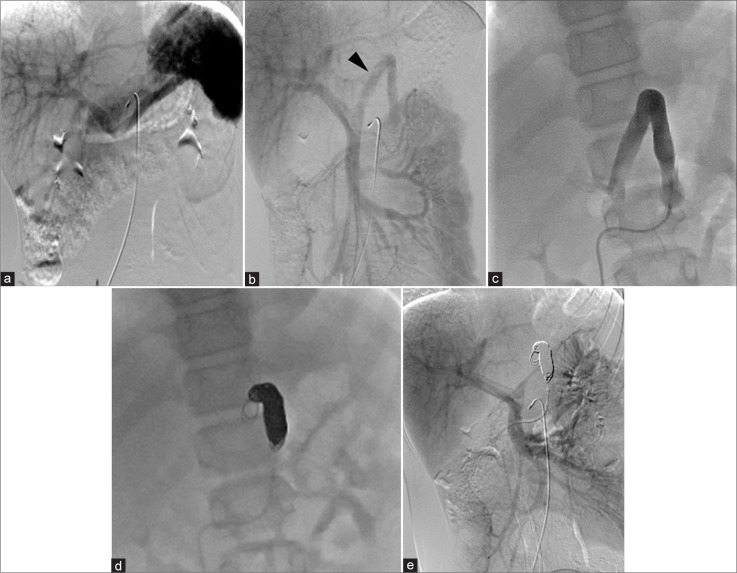

先天性门静脉系统分流(CPSS)是一种罕见的血管异常,其中门静脉血液流入体循环而不经过肝脏。大约每3万到5万例活产婴儿中就有1例。我们报告了一位11岁的肝外CPSS患者,并进行了长期随访。最初的临床表现没有明显的异常。随后的评估显示氨(NH3)和总胆汁酸(TBAs)略有升高。2岁和11岁时两次血管造影证实门静脉和左肾静脉分流,随着患者年龄的增长,血流优势逐渐从腹腔动脉-脾静脉系统转移到肠系膜上动脉-肠系膜上静脉系统。由于并发症的风险,我们进行了经导管分流栓塞,使用12个线圈实现了完全的分流栓塞。栓塞后,NH3和TBA水平恢复正常,患者无症状。该病例强调了CPSS干预时机的重要性,特别是在血流动力学变化的情况下,并强调了儿科CPSS最佳干预时机的进一步研究的必要性。

Congenital portosystemic shunt (CPSS) is a rare vascular anomaly in which portal vein blood flows into the systemic circulation without passing through the liver. They occur in approximately 1 in 30,000-50,000 live births. We present an 11-year-old patient with an extrahepatic CPSS managed with long-term follow-up. The initial clinical presentation showed no significant abnormalities. Subsequent assessments revealed slightly elevated ammonia (NH3) and total bile acids (TBAs). Two times angiography at the ages of 2 and 11 years confirmed a shunt between the portal vein and left renal vein, with a gradual shift in blood flow dominance from the celiac artery-splenic vein system to the superior mesenteric artery-superior mesenteric vein system as the patient aged. Due to the risk of complications, transcatheter shunt embolization was performed, utilizing 12 coils to achieve complete shunt embolization. Post-embolization, NH3, and TBA levels normalized, and the patient remained asymptomatic. This case highlights the importance of timing in CPSS intervention, particularly with shifting hemodynamics and underscores the need for further studies on optimal intervention timing in pediatric CPSS.